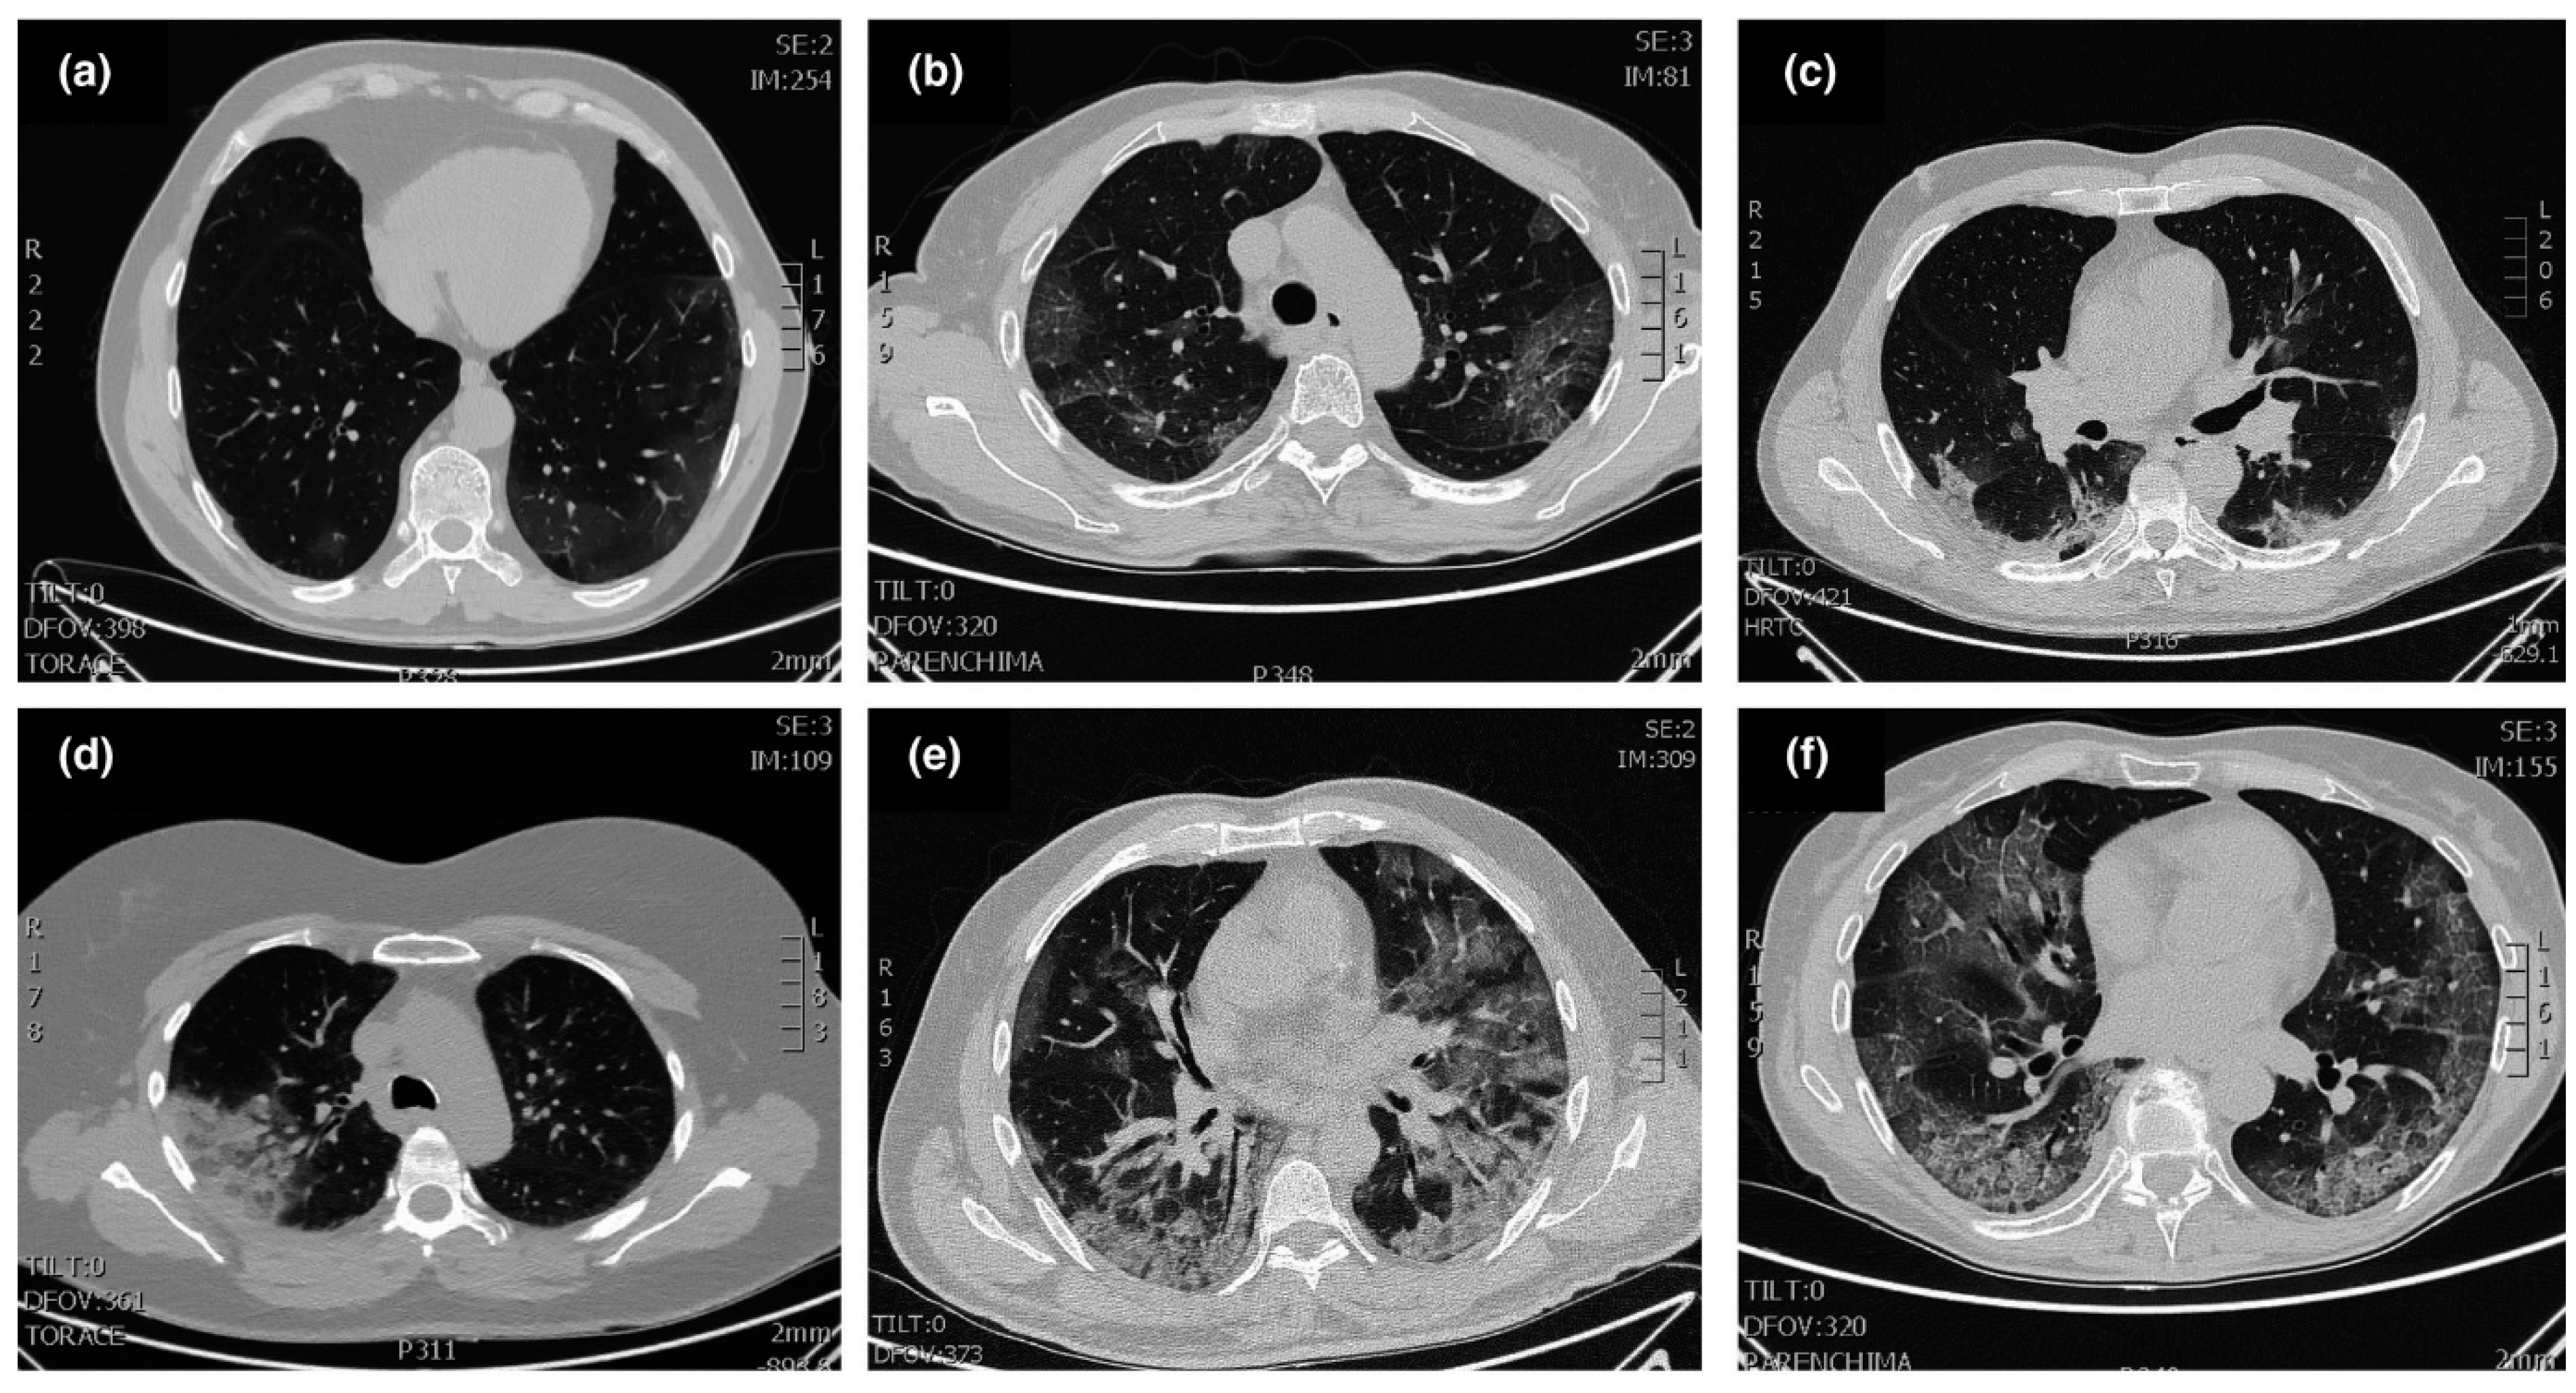

- Ai, T.; Yang, Z.; Hou, H.; Zhan, C.; Chen, C.; Lv, W.; Tao, Q.; Sun, Z.; Xia, L. Correlation of chest CT and RT-PCR testing for coronavirus disease 2019 (COVID-19) in China: A report of 1014 cases. Radiology 2020, 296, 32–40. [Google Scholar] [CrossRef] [Green Version]

- Kanne, J.P.; Little, B.P.; Chung, J.H.; Elicker, B.M.; Ketai, L.H. Essentials for radiologists on COVID-19: An update—Radiology scientific expert panel. Radiology 2020, 296, 113–114. [Google Scholar] [CrossRef] [PubMed] [Green Version]